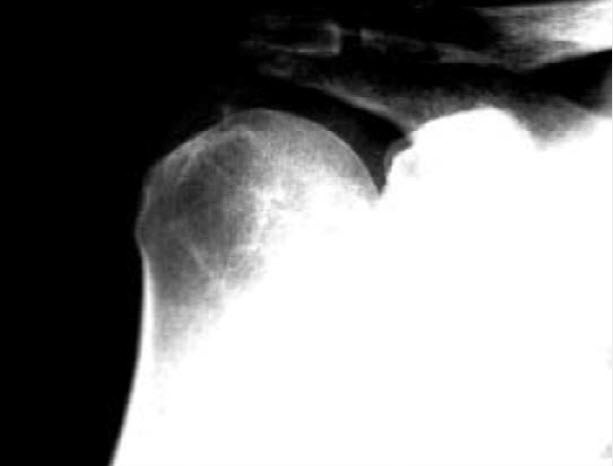

Höchst effektive SchmerzlinderungDie BTL Stosswellentherapie ist eine neue nicht-invasive Lösung für chronische muskuloskeletale Schmerzen. Extrakorporale Stosswellentherapie wird am häufigsten in der Physiotherapie, Orthopädie und Sportmedizin verwendet. Hauptsächliche Anwendungsgebiete sind die Behandlung von chronischen Muskel- und Sehnenerkrankungen, Rücken- und Nackenschmerzen. Zu den häufigsten Indikationen zählen: Schmerzen im Schulterbereich, Epikondylitis, Rückenschmerzen, Achillessehnenschmerzen, Patellasehnenentzündung, Triggerpunkte. Bei der Behandlung mit Stoßwellen werden akustische Wellen ins Gewebe geleitet, deren Energie schmerzhafte Stellen im Binde- oder Myoskeletalgewebe mit subakuten, subchronischen und chronischen Zuständen heilt. Diese Energie regt Heilungs-, Regenerations- und Reparaturmechanismen der Sehnen und des Weichteilgewebes an. Das BTL Stoßwellentherapie-Gerät ist das stärkste und kompakteste auf dem Markt erhältliche Stoßwellengerät. Anwendungen- Therapie von Schmerzen im Schulterbereich - Therapie vom Fersensporn (CALCAR CALCANEI, FASCIITIS PLANTARIS) - Therapie von Tennis Ellbogen (EPIKONDYLITIS RADIALIS/ULNARIS) - Therapie von Schmerzen der Achillessehne (ACHILLODYNIE)

ANALGETISCHER EFFEKT – SCHMERZBEKÄMPFUNG ABBAU VON MUSKELSPANNUNG, HEMMUNG VON SPASMENHyperämie ist einer der Haupteffekte der Stoßwellentherapie im Körper. Sie führt zu einer besseren Energieversorgung der hypertonischen Muskeln und deren Sehnen. Außerdem wird die pathologische Interaktion zwischen Aktin und Myosin verringert. Dies führt zu einer Verminderung von Muskelspannung, die oft schmerzhaft für den Patienten ist. VERBESERTE AUSSCHÜTTUNG VON „SUBSTANZ P“Die Aktivität von Substanz P (Schmerzmediator und Wachstumsfaktor) führt zur Stimulation von afferenten nozizeptiven Fasern. Sie verbessert ebenso die Ödementwicklung und unterstützt die Sekretion von Histaminen. Die Reduzierung von deren Konzentration lindert den Schmerz im betroffenen Bereich und verringert die Entwicklung von Ödemen. Beschleunigung der HeilungERHÖHUNG DER COLLAGEN-PRODUKTIONDie Produktion von ausreichend Collagen ist eine notwendige Vorbedingung für den Gewebewiederherstellungsprozess. Die Stoßwellentherapie stimuliert Collagenherstellung in tieferen Gewebsschichten. VERBESSERTER METABOLISMUS UND MIKROZIRKULATIONDie Stoßwellentherapie beschleunigt die Entfernung von nozizeptiven Metaboliten, unterstützt Sauerstoffversorgung und versorgt das beschädigte Gewebe mit Energie. Es fördert die Entfernung von Histamin, Laktat und anderen nozizeptiven Stoffwechselprodukten, die meist sauren Charakters sind. WIEDERHERSTELLUNG DER BEWEGLICHKEITAUFLÖSUNG VON VERKALKTEN FIBROBLASTEN

Die Stoßwellentherapie löst die verkalkten Fibroblasten auf und beginnt anschließend die biochemische Entkalkung einer primären Exostose oder sekundären Symptomen von Arthrose